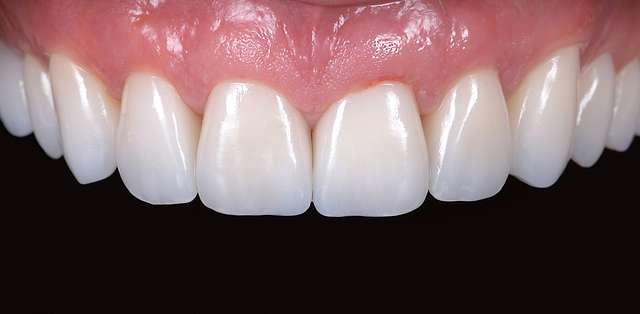

Grefe pentru corectia nivelului si a retractiei gingivale

Grefe pentru corectia culorii gingivale

Focusul este pe cel mai bun rezultat final, atat din punct de vedere estetic cat si durabil. In cazurile complexe cu indicatii deosebite, Dentcof dispune si de logistica necesara colaborarii cu specialisti internationali. Vezi echipa

Fiecare caz este planificat digital, si este executat cu cea mai potrivita procedura. Rationamentul folosit pentru selectia celei mai potrivite proceduri, consta in raportul dintre cel mai longeviv rezultat si cea mai putin invaziva procedura. Chirurgia ghidata